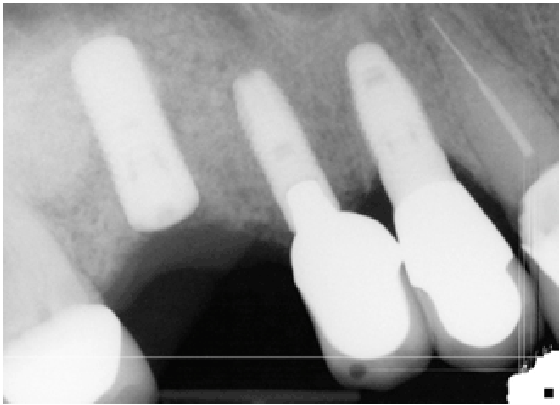

本病例系列的数据集包括使用侧窗入路技术接受窦道增强术的患者,这些患者发生了巨大的Schneiderian膜穿孔(>10 mm)并已报告(图1a-1e)。在这些患者中,窦底以下必须有< 5mm的嵴骨,才能考虑纳入本研究。共选取8例患者(10例鼻窦,1例女性,7例男性),年龄35 ~ 75岁,平均53.5岁。

图1:术前:咬合视图

图1 b:op:横向视图